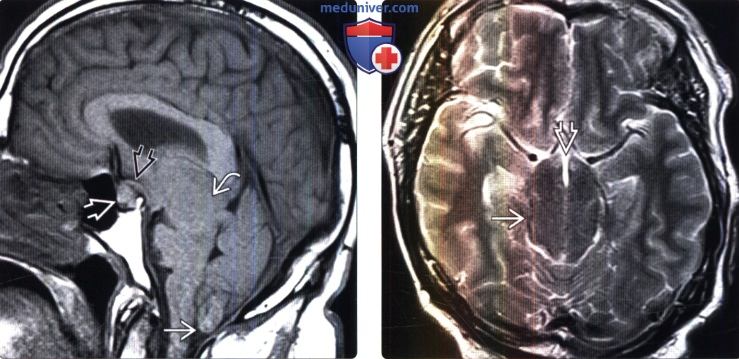

Раздел: Образы вокруг